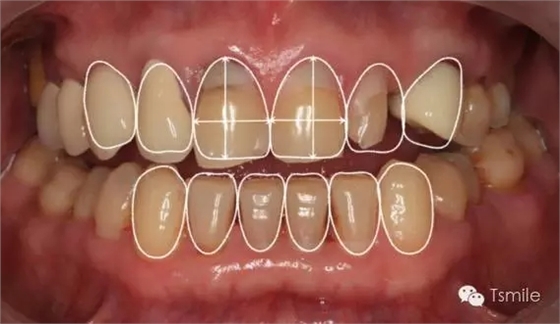

在前牙的美學(xué)分析中有四個最重要的美學(xué)影響因素,稱之為前牙美學(xué)四要素。包括上中切牙切緣的位置、上中切牙臨床冠的寬長比、上中切牙齦緣的位置、上前牙的寬度比例。這四要素是影響前牙美學(xué)的主要因素,根據(jù)這四要素就可以簡單、快速、準(zhǔn)確地分析患者前牙存在的美學(xué)缺陷。根據(jù)這四因素就可以準(zhǔn)確、直接地進(jìn)行患者前牙的美學(xué)修復(fù)設(shè)計。

美學(xué)表達(dá)就是要把醫(yī)師大腦中形成的美學(xué)設(shè)計思想,采用各種方法準(zhǔn)確、真實(shí)、直觀地表達(dá)給患者,進(jìn)行醫(yī)患溝通,進(jìn)行口內(nèi)診斷性美學(xué)修復(fù)。在口內(nèi)根據(jù)患者主客觀反應(yīng)進(jìn)行調(diào)改,形成最終的美學(xué)修復(fù)設(shè)計。最后進(jìn)行醫(yī)技溝通,指導(dǎo)技師完成修復(fù)體制作。美學(xué)表達(dá)的方法有:數(shù)碼圖像設(shè)計(如DSD)、診斷飾面(Mock-up)、診斷蠟型(Wax-up)、模型外科、臨時修復(fù)體等。